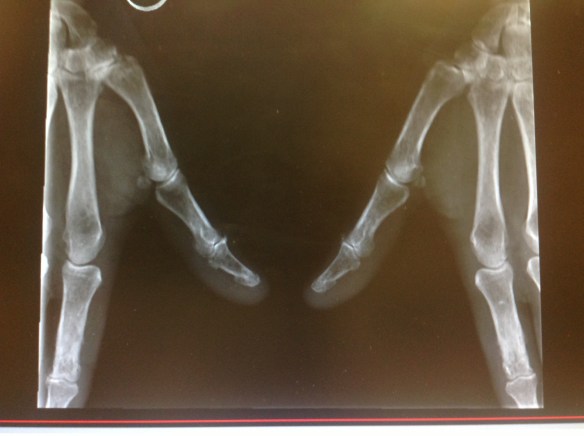

El origen más frecuente de dolor en la base de la columna del pulgar es la Rizartrosis. La rizartrosis es la artropatía degenerativa de la articulación trapeciometacarpiana. Se classifica en 4 grados según los hallazgos radiológicos ( ver el post sobre Cómo realizar proyecciones radiológicas correctas de la base del pulgar).

Pero el dolor mecánico en la base del pulgar también puede tener su origen en la articulación escafotrapeciotrapezoidea. En este caso el dolor es más proximal , justo a nivel del borde donde se inicia el reborde de la eminencia tenar. El dolor se exacerba con la extensión de la muñeca asociada a desviación radial ( por ejemplo al hacer apoyo sobre las manos para levantarse del sofá).No es infrecuente que la paciente tenga historia de ganglión volar del carpo paraarterial radial.

A menudo pueden asociarse ambas:rizartrosis con artropatía escafotrapeciotrapezoidea. Se denomina entonces artropatía peritrapecial. Debe valorarse siempre su presencia antes de iniciar el tratamiento de una rizartrosis pues éste será Diferente.